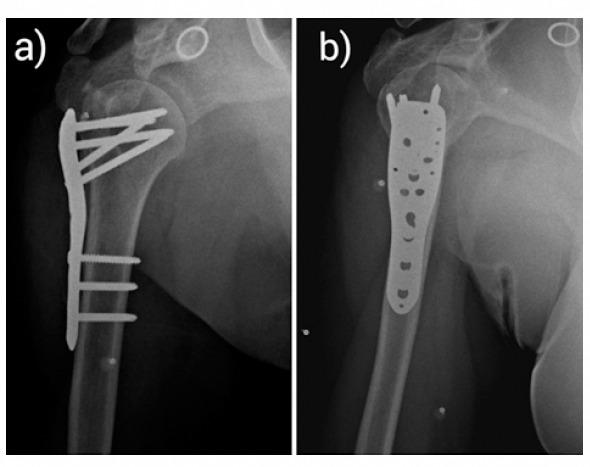

We report a unique fracture pattern consisting of combined greater and lesser tuberosity of the proximal humerus (PH) with intact humeral head and shaft in a 32-year-old female. Routine radiographs and computed tomography scan with three-dimensional reconstruction were advised for better understanding of the fracture pattern, later managed by open reduction and fixation with PH locking plate. The patient has excellent clinical, radiological, and functional outcome at the end of 2 years follow-up.

This is one among the few case reports highlighting this unique variant of PH fracture, not much has been described in the literature about this injury. Anatomic reconstruction of the fractured tuberosities combined with stable construct by PH locking plate facilitates optimum bone healing and aggressive shoulder rehabilitation.

我们报告了一名32岁女性的独特骨折类型,其近端肱骨大结节与小结节联合骨折,肱骨头和骨干完整。建议进行常规X线片和三维重建计算机断层扫描以更好地了解骨折类型,随后通过切开复位并用肱骨近端锁定钢板固定进行治疗。在2年随访结束时,患者获得了良好的临床、影像学和功能结果。

这是少数几例突出这种独特的近端肱骨骨折变体的病例报告之一,关于这种损伤的文献描述不多。骨折结节的解剖重建结合肱骨近端锁定钢板的稳定结构有助于实现最佳的骨愈合和积极的肩部康复。